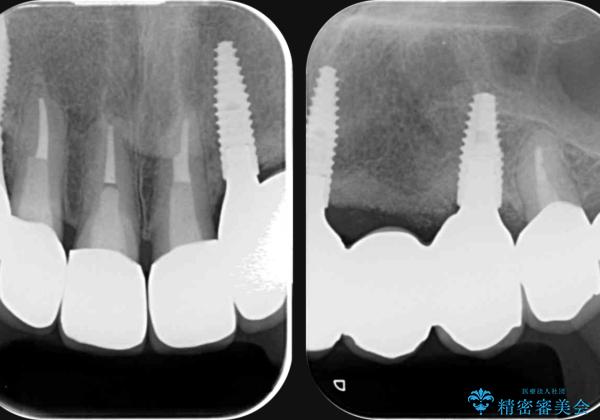

抜去を行ったのち、インプラント治療を計画しますが骨量が少ないため、まず骨の造成を行ったのちインプラントを埋入していく治療計画としました。

インプラント治療を行ったことでしっかりとした咬合関係を確立することができました。